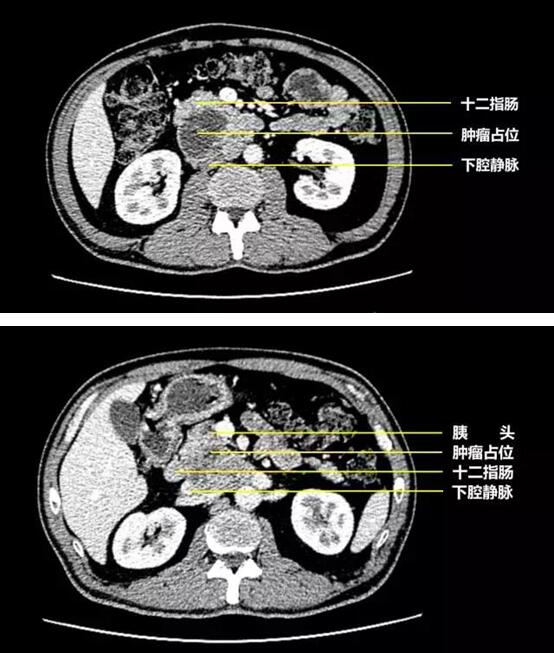

然而天有不测风云,人有旦夕祸福。年仅56岁的黄某,于数天前参加单位体检,得到一份腹部CT报告示: 腹腔内覆膜后间隙见一团块状混杂密度肿块影,与胰腺头部分界欠清,大小约48*77mm,边界清晰,其内见分隔,增强后分隔及实性部分明显强化,胰管未见明显扩张;下腔静脉受压与肿块分界不清,胰头及十二指肠动静脉向前推移,被诊断为患“巨大异位副神经节瘤”,这对于一个家里主要的经济来源的壮年来说,无疑是晴天霹雳。因病情十分复杂,转辗多家医院,众多大型医院著名专家们都说肿瘤巨大侵犯了人体最重要的四根血管已无法切除。

经过详细的术前评估、积极的术前准备,于2016年6月14日手术,术中探查发现肿瘤位于胰头后方,大小约7X5cm;其右前方为十二指肠、正前方为胰头、左前方为肠系膜上动脉,肿瘤向后压迫下腔静脉、左肾静脉,并向后伸入腹主动脉与下腔静脉之间的间隙,与左肾静脉及右肾动脉密切粘连,肿瘤左后方为腹主动脉。